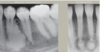

What is this disease?

Simple Bone Cyst

Also known as

1.) Solitary Bone Cyst.

2.) Traumatic Bone Cyst.

3.) Idiopathic Bone Cyst.

4.) Hemorhhagic Bone Cyst.

Remember radiographic feature

tend to Scalop between teeth

Treatment includes surgical curettage- spontaneous healing has been reported.

What is the radiographic finding?

Residual Cyst